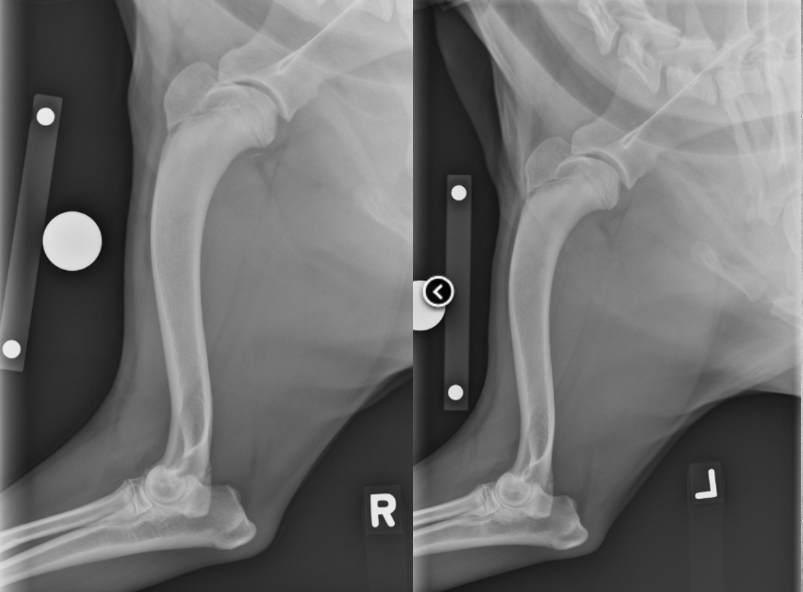

8 months old female German Shepherd

Painful elbows

Both elbows: the anconeal process is ununited, the margins of the anconeal process and olecranon are markedly irregular and periosteal proliferation is present.

Marked intramedullary sclerosis of the olecranon and subtrochlear region of the proximal ulna is visible.

Diagnosis: Ununited anconeal process (UAP) and panosteitis of the ulnas.